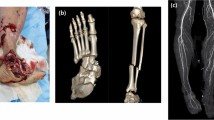

Careful excavation of the burial feature containing TB1 revealed the complete absence of the left foot (Fig. 3 and Extended Data Figs. 3 and 4). Recovered left tibia and fibula shaft fragments, found flexed underneath the left femur, presented unusual distal bony growth (Fig. 3 and Extended Data Figs. 4 and 5). The opposite leg was articulated, with all right foot bones (n = 26) recovered within the grave (Fig. 3a). Remodelled bone covers the amputation surfaces identified on the left distal tibia and fibula shaft fragments, demonstrating healing (Fig. 3b–f, Extended Data Figs. 4 and 5 and Supplementary Information). This indicates that the distal third of TB1’s lower leg was removed through deliberate surgical amputation at the position of the distal tibia and fibula shafts. The trauma pattern observed is not consistent with clinical descriptions of non-surgical amputation, except in cases of modern trauma in which a large metal blade or a mechanical process has been involved14,15,16,17. Non-surgical amputations, commonly as a result of accidents, do not cause clean oblique sectioning and are not clinically recorded to sever the lower limb of both the tibia and fibula, as is the case for TB1. Blunt-force trauma from an accident or an animal attack typically causes comminuted and crushing fractures18, features that are absent from the clearly simple and oblique amputation margin of TB1. Amputation as punishment is considered unlikely, particularly given the careful treatment of the individual in life after the amputation and in burial, which is not consistent with someone considered deviant19. Completely remodelled lamellar bone has enclosed the inferior margin of the fibula (Fig. 3e,f), indicating that TB1 died a minimum of 6–9 years after the initial trauma—confirming that this was not a fatal pathology20,21,22. There is no evidence of infection in the left limb, the most common complication of an open wound without antimicrobial treatment. The lack of infection further rules out the probability of animal attack, such as a crocodile bite, because an attack has a very high probability of complications from infection owing to microorganisms from the animal’s teeth entering the wound23. The partial consolidation of the bone between the left tibia and fibula and complete closure of the distal end of the left fibula (Fig. 3b,e,f and Extended Data Figs. 4 and 5) are consistent with late-stage amputation changes14. The small size of the left tibia and fibula compared with the right suggests a childhood injury, as the bones did not continue growing (Fig. 3a). The severe bone thinning of the left tibia and fibula is also suggestive of the heavily restricted use of the left leg resulting in musculoskeletal disuse atrophy22 (Extended Data Fig. 4). Some thinning of the cortical margins of the right tibia suggests that TB1 was rarely ambulatory owing to the incapacitating nature of the injury to the lower left leg (Extended Data Fig. 4).

a, TB1 left and right legs with pelvic girdle, demonstrating the complete absence of the distal third of the left lower leg. b, Left tibia and fibula showing the amputation surface, atrophy and necrosis. The bone surface is more porous because lysis occurred to remove the dead bone (necrosis). c, Radiograph of the left tibia and fibula. d–f, Remodelled bone covering the amputation surfaces, demonstrating healing after the amputation. d, Left tibia medial aspect. e, Left tibia medial aspect. f, left fibula anterior aspect. Images in d–f taken using an Olympus DSX1000 digital microscope. Scale bars, 5 cm (a), 5 mm (b and c) and 2 mm (d–f).